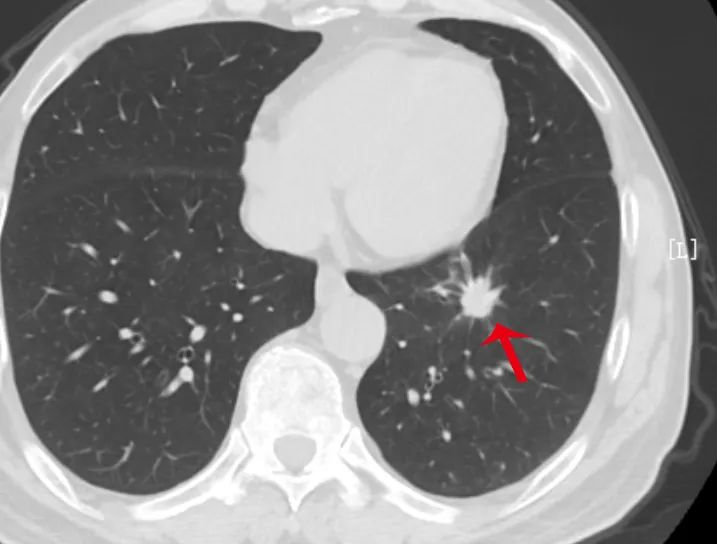

长相越是古怪的结节,越需要高度重视,尤其是出现分叶、毛刺、胸膜牵拉、含气细支气管征和小泡征、偏心厚壁空洞等征象。

检查出小结节后,医生往往会建议定期复查,若结节短期内(3-6 个月)迅速增大或是长期不断增大,需警惕恶性。